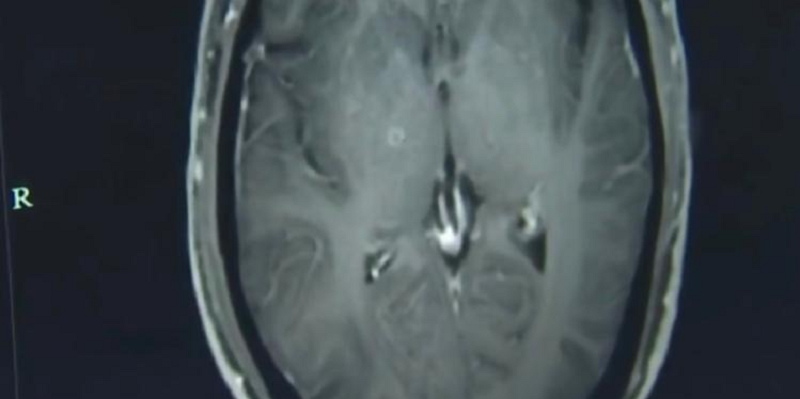

Imagem da ressonância magnética do cérebro do chinês com lesões e aproximadamente 700 ovos de tênias (Foto:Reprodução / Hospital da Universidade de Zhejiang)

O chinês Zhu Zhongfa, de 46 anos, teve um quadro forte de convulsões, foi hospitalizado e os médicos estavam com dificuldade de dar um diagnóstico. Com uma ressonância, a equipe detectou cerca de 700 ovos de tênia no cérebro do homem, que admitiu ter ingerido um caldo com carne de porco de origem duvidosa.

Na primeira vez que foi hospitalizado, Zhu havia sentido fortes dores de cabeça, mas recusou o tratamento por não querer gastar dinheiro. Os sintomas persistiram e o chinês foi hospitalizado pela segunda vez, quando os médicos fizeram uma ressonância magnética e descobriram centenas de calcificações e lesões no cérebro de Zhu.